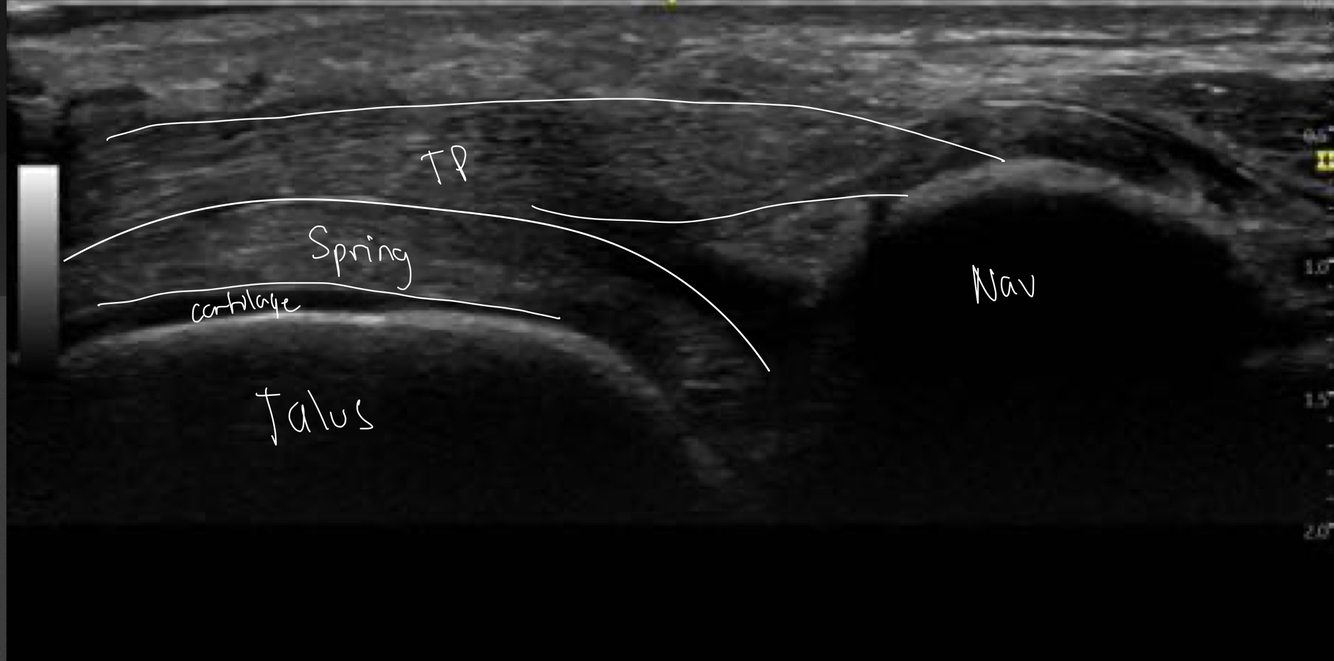

13

Q

Identifie les structure sur l’image

Dites dans quelle region du pied il se situe

A

Nous sommes en médial de la cheville